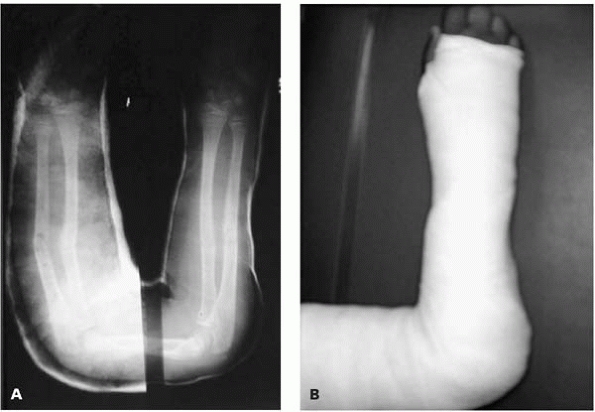

![]() |

|

▪ FIGURE 4-15 Don’t immediately attribute a wide retropharyngeal space (red arrow) to trauma and swelling—it may be due to crying, as seen in this image.

trauma evaluations. If these initial films are normal, but the child

step. Don’t be fooled by certain false positives in children—that

retropharyngeal “swelling” due to crying (Fig. 4-15) and C2-3 pseudosubluxation. A CT scan